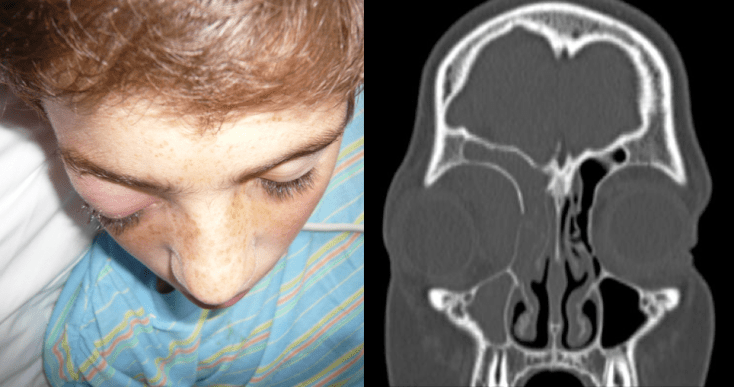

les signes d’impact et de fracture : tuméfaction et ecchymose

- exophtalmie unilatérale de l’hématome orbitaire

- hématome en lorgnette si fracture unilatérale

- « yeux de raton-laveur » (raccoon’s eyes) si bilatérale